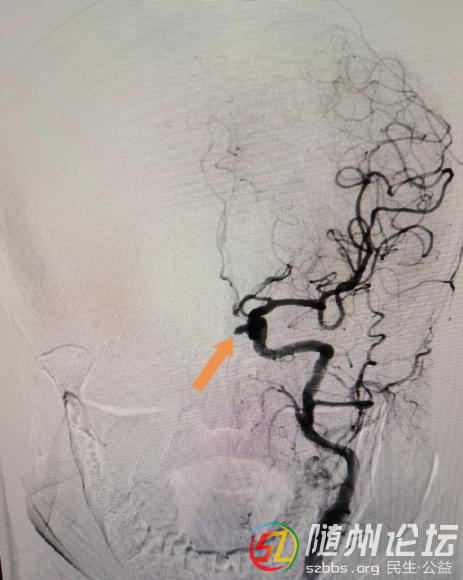

患者黃某某,因“頭痛伴惡心1天”入院,行急診顱腦CT顯示:蛛網(wǎng)膜下腔出血?;颊呒膊⊥话l(fā)且無外傷史,遂考慮動脈瘤破裂出血所致。入病房后,完善相關輔檢,急診行頭頸部CTA檢查后顯示:頸內動脈C6段動脈瘤。

手術前

手術后

經(jīng)過醫(yī)護團隊的努力,手術非常順利,術后造影顯示:頸內動脈瘤栓塞致密,載瘤動脈通暢,麻醉復蘇后患者無任何并發(fā)癥。經(jīng)過醫(yī)護團隊的精心治療、護理,患者完全治愈出院,并送來錦旗表達對醫(yī)院和科室醫(yī)護人員的感謝。